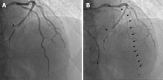

Coronary spasm is caused by a transient coronary narrowing due to the constriction of epicardial coronary artery, which leads to myocardial ischemia. More than 50 years have passed since the first recognition of coronary spasm, and many findings on coronary spasm have been reported. Coronary spasm has been considered as having pivotal roles in the cause of not only rest angina but also exertional angina, acute coronary syndrome, and heart failure. In addition, several new findings of the mechanism of coronary spasm have emerged recently. The diagnosis based mainly on coronary angiography and spasm provocation test and the mainstream treatment with a focus on a calcium-channel blocker have been established. At a glance, coronary spasm or vasospastic angina (VSA) has become a common disease. On the contrary, there are several uncertain or unsolved problems regarding coronary spasm, including the presence of medically refractory coronary spasm (intractable VSA), or an appropriate use of implantable cardioverter defibrillator in patients with cardiac arrest who have been confirmed as having coronary spasm. This editorial focused on coronary spasm, including recent topics and unsolved problems.